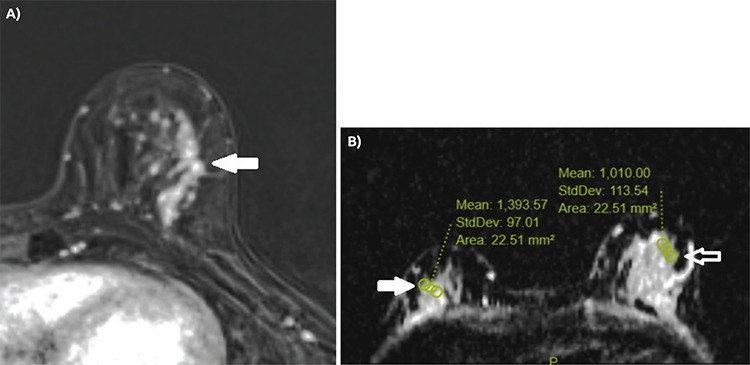

Results: Among the lesions, 44 were double HRc-positive (ER and PR-positive), 13 were single HRc-positive (ER-positive and PR-negative or ER-negative and PR-positive) and 22 were double HRc-negative (ER and PR-negative). The presence of symptom (p = 0.029), the presence of comedo necrosis (p = 0.005) and high histological grade (p<0.001) were found to be associated with ER and PR negativity. Amorphous microcalcifications were more commonly observed in the double HRc-negative group, while linear calcifications were more prevalent in both double and single HRc-positive groups (p = 0.020). Non-mass enhancement (NME) with a linear distribution was significantly more common in double HRc-negative lesions (38%), and NME with a segmental distribution in both double (43%) and single (50%) receptor-positive lesions (p = 0.042). Evaluation of DWI findings revealed that a higher lesion-to-normal breast parenchyma apparent diffusion coefficient (ADC) ratio statistically increased the probability of HRc positivity (p = 0.033).

Conclusion: Certain clinicopathological, mammography, and MRI features, along with the lesion-to-normal breast parenchyma ADC ratio, can serve as predictors for HRc status in DCIS lesions.